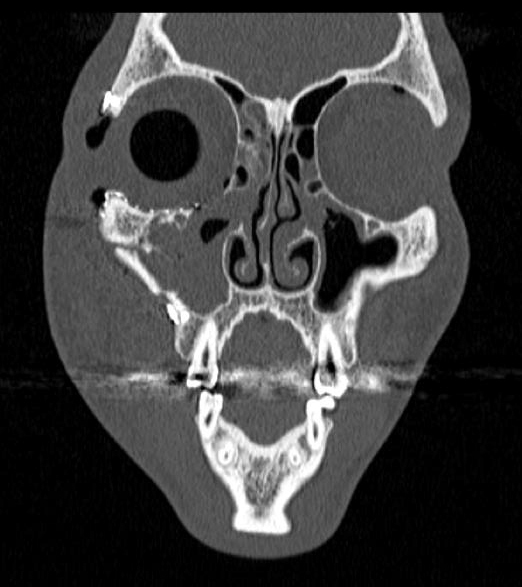

De garde, vous êtes appelé en salle de surveillance post-interventionnelle (SSPI) dans votre hôpital où vient d'être admis un patient conduit sur place par le service d'aide médicale d'urgence (Samu). Il s’agit d’un jeune homme de 20 ans, Monsieur D. Il aurait été victime, entre autres, d’un tir de Flash-Ball lors d’une rixe. Le projectile l’a atteint au niveau de la pommette et de l’orbite droites. Il présente une plaie de la région jugale haute, un œdème des paupières supérieure et inférieure. Vous ne visualisez pas le globe oculaire spontanément. Il est hémodynamiquement stable.

Traumatisme orbitaire = à risque de fracture des parois de l’orbite et donc d’incarcération d’un muscle oculomoteur.